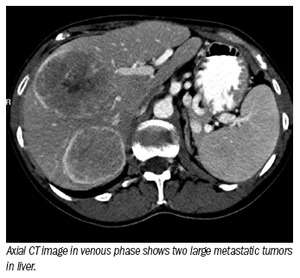

Multimodality tour de force enables various specialists to safely administer radiation directly into liver tumors